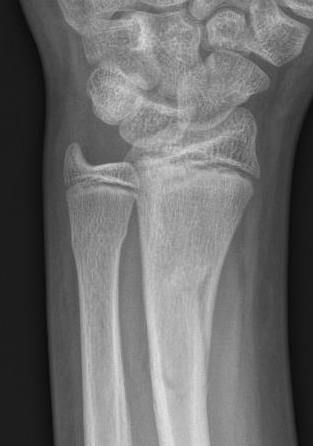

Distal radius buckle fracture

- torus / buckle fractures: compression and unicortical bend / buckle of one cortex with no clear break